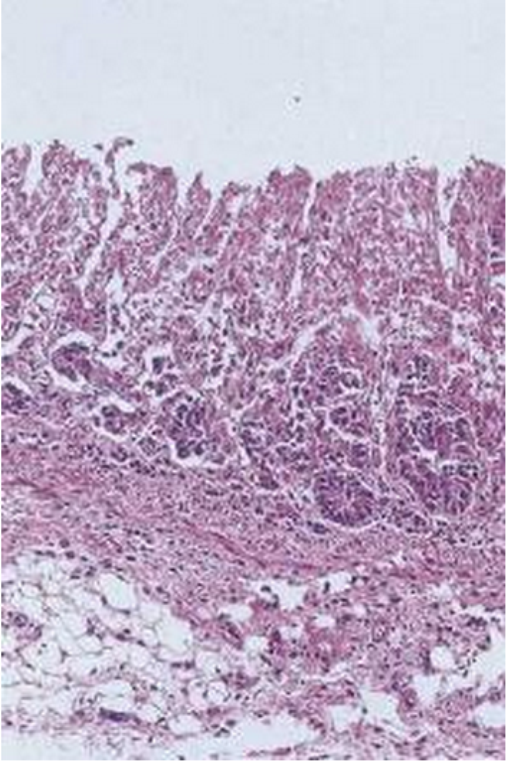

Fig. 1. Muestra de intestino delgado normal, correspondiente a un cerdo recién necropsiado y con una fijación inmediata de las muestras digestivas. Tinción de Hematoxilina y Eosina

Fig. 2. Muestra de intestino delgado autolítico. Nótese la pérdida de estructura y la imposibilidad de identificar la estructura cripta-vellosidad. La autolisis empieza a ser un efecto evidente a las 2 horas post-mortem y complica / imposibilita el diagnóstico anatomo-patológico de las muestras estudiadas. Hematoxilina y Eosina.